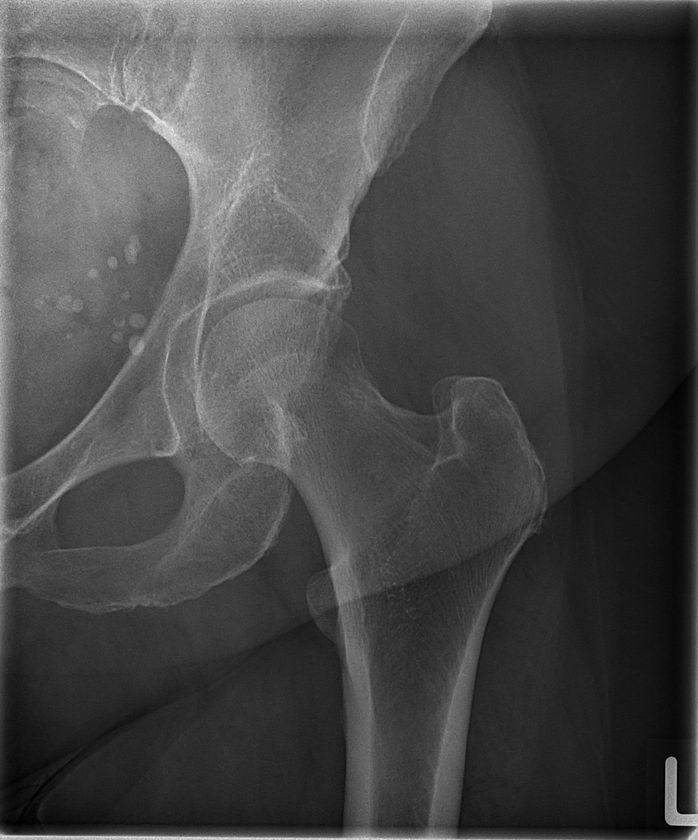

画像5

TRB 9020Hで撮影した大腿骨レントゲン写真

※84 kV HP mode 1.8 mAs, 0.12 sec Exposure Index: 367